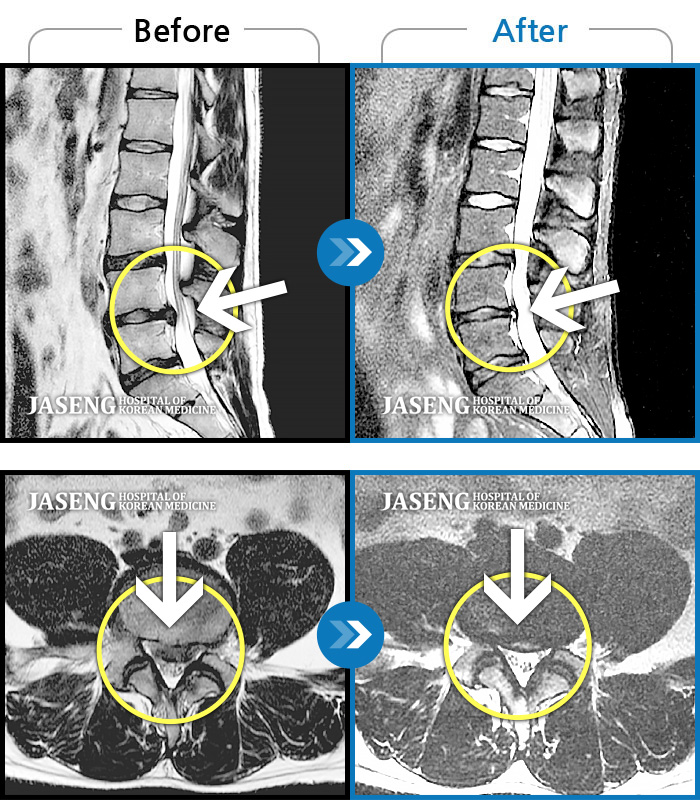

MRI 결과는 추간판협착증 2군데와 추간판탈출되어 터져서 디스크가 좌측으로 흘러내려 좌측 신경을 넓게 누르고 있는 곳이 1군데로 예상보다 심각한 상태였더군요.